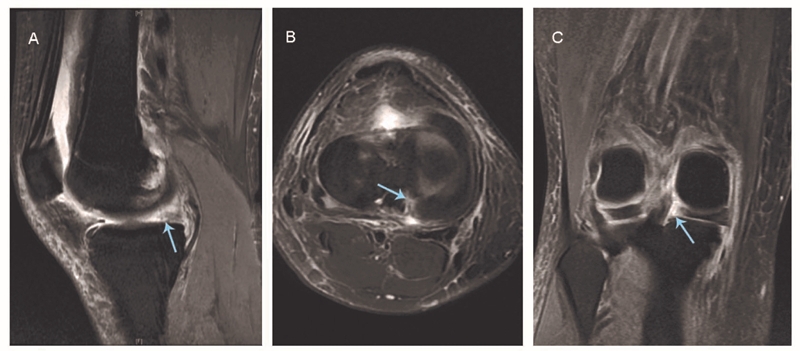

图1 磁共振成像显示内侧半月板后根撕裂

A:矢状位无正常半月板信号:鬼影征(箭头所示);B:轴位图像显示内侧半月板后根部放射状线形缺损(箭头所示);C:冠状位表现为内侧半月板后内缘走形突然中断(箭头所示)

磁共振成像(MRI)是诊断MMPRTs及其伴随病变的首选影像学检查方式,然而,MRI对于MMPRTs诊断的准确性依赖于图像质量以及放射科和外科医生的技术。MMPRTs的诊断与评估通常采取T2加权相的冠状位、矢状位和轴位图像。当怀疑MMPRTs时,MRI应评估三个主要征象:①矢状位无正常半月板信号:鬼影征;②轴位上表现内侧半月板后根部区域放射状线形或圆形缺损区;③冠状位表现为内侧半月板后内缘走形突然中断,伴随内侧半月板向外突出超过3mm。据报道,这三种症状同时使用时具有较高的敏感性和特异性。